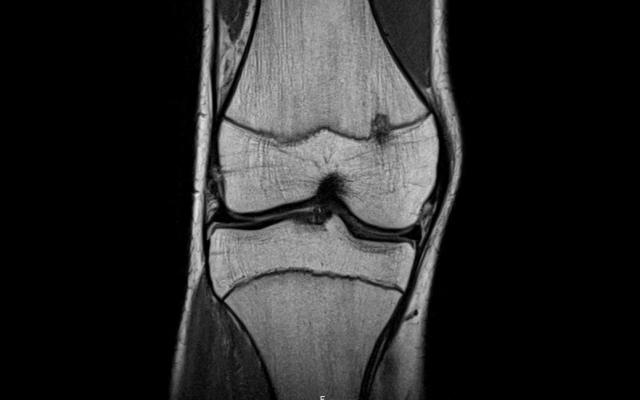

Op de polikliniek Orthopedie zagen wij een 16-jarige voetballer met sinds een week spontaan ontstane, hevige pijn aan de mediale zijde van de linker knie. Er was geen sprake van zwelling, instabiliteit of slotklachten. De patiënt had geen nachtpijn. Het lichamelijk onderzoek van de knie was niet afwijkend. Gezien de aanhoudende, hinderlijke pijn werd een MRI vervaardigd om meniscus- of kraakbeenletsel uit te sluiten. De MRI toonde geen intra-articulaire afwijkingen. Wel werd er focaal beenmergoedeem (‘focal periphyseal oedema’, FOPE) gezien aan de mediale zijde bij de groeischijf van het distale femur (figuur 1).

FOPE betreft een fysiologische reactie bij…